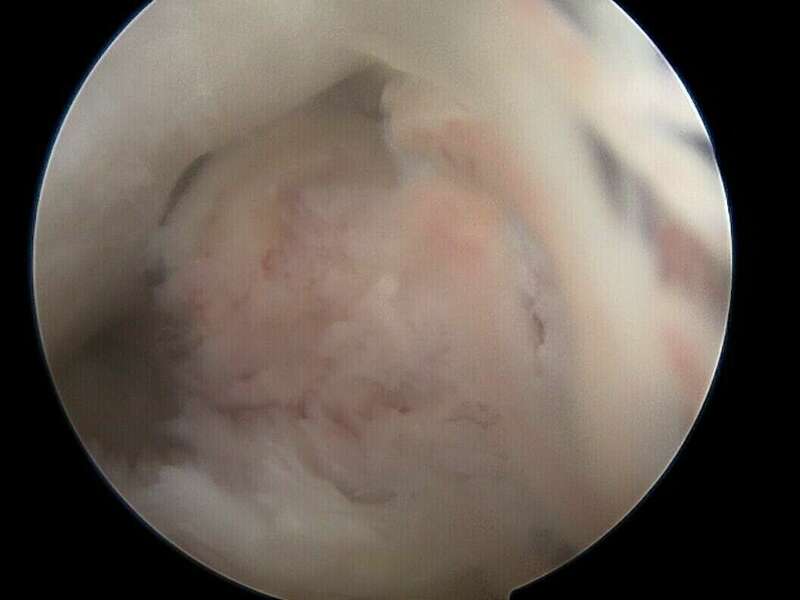

En l’absence d’évolution spontanément favorable, le traitement est systématiquement chirurgical et consiste à retirer ce nodule d’arthro-fibrose sous arthroscopie au cours d’une hospitalisation de courte durée en Chirurgie Ambulatoire. Lors de l’intervention chirurgicale, le chirurgien s’assurera de la récupération de l’extension complète du genou.

Les résultats de ce type d’intervention sont très satisfaisants avec une diminution notable des douleurs et la récupération d’une extension complète. Elle permet au patient de poursuivre la rééducation de son genou pour pouvoir reprendre ses activités professionnelles et sportives.